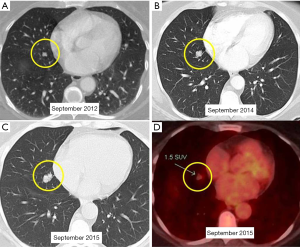

A 52-year-old lifetime non-smoker female with no significant past medical and surgical history presented for a routine follow-up of a right lower lobe solitary pulmonary nodule. This nodule was incidentally detected on a CTA chest performed in 2012 to rule out a pulmonary embolus (Figure 1). After the initial scan in 2012, the patient was lost to follow-up for two years and presented again in 2014. CT scan of the chest now showed that the right lower lobe non-calcified pulmonary nodule had grown in size (Figure 1B). A one year follow-up with a CT scan of the chest showed that the lung nodule had doubled in size over three years, highly suspicious for malignancy (Figure 1C). PET/CT showed mild uptake in the enlarging pulmonary nodule (Figure 1D). Subsequently, a CT-guided biopsy of the nodule revealed a carcinoid tumor (Figure 2). Next, the patient underwent a right middle lobectomy with an uncomplicated recovery (Figure 3A). Pathology results showed a well-differentiated NET with more than 2 mitoses per 10 hpf with no atypia or necrotic foci (Figure 3B,C), consistent with an atypical lung carcinoid. Tumor cells stained positive for cytokeratin 7, TTF-1, chromogranin A (CgA), synaptophysin, and negative for CK20, with Ki-67 proliferation index of 1% (Figure 3D), consistent with a lung carcinoid. Follow-up imaging showed no local spread or distant metastases. The patient is disease free till date, consistent with cure.